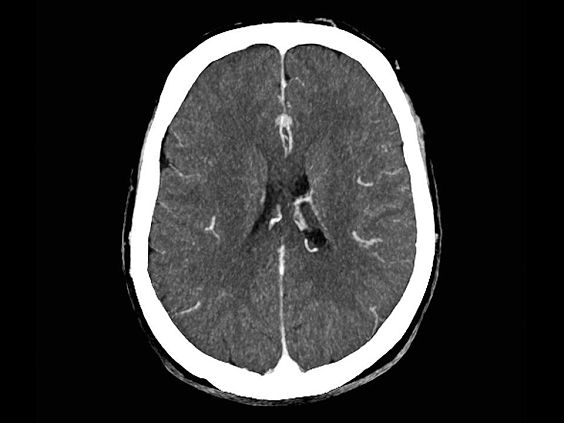

Клинические изображения

SOMATOM go.Up оптимизирует качество изображений и снижает лучевую нагрузку в рутинных неврологических исследованиях. SOMATOM go.Up отличается высокой скоростью сканирования и высоким качеством полученных изображений, что повышает качество диагностики особенно мелких сосудистых структур.